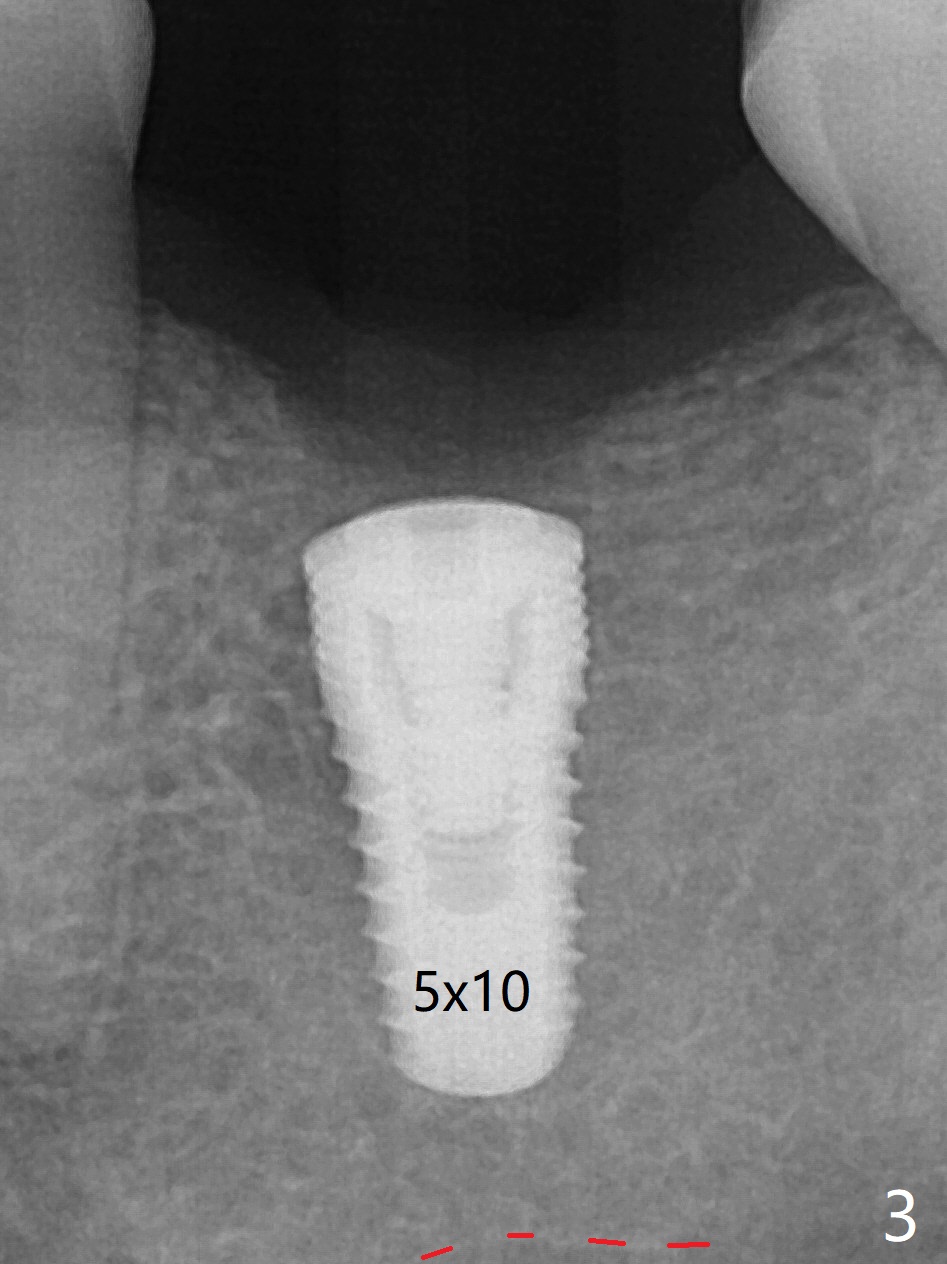

50岁男,左下6牙槽骨宽,但是骨密度低。开始使用导板和小钻头,植体(5x10毫米)扭力大,改用正常钻头,扭力仍高,使用功螺纹后,扭力~35Ncm;使用6毫米profile drill后,放置6x4(2)毫米愈合基台,后者好像与近中牙槽嵴接触(图一:*)。取出基台不顺利,接着放置5x5(3)毫米基台,无法拧紧,取出时,把植体带出来。最后把植体推入钻洞,没有任何扭力,放置愈合帽和Osteogen Plug,缝合(图二,三),牙周敷料,但愿能愈合。在骨质密度低时,放置不合适基台(太宽,太短),可能造成植体松动,脱落,失败。术后十二天牙周敷料脱落,伤口正在愈合(图四(曾经使用环形刀))。术后四个月植体仿佛已经整合(图五),切开放置6.2x5(3)毫米愈合基台,好像与近中牙槽嵴接触太紧(图六)。12天后放置修复基台,似乎就位(图七),其实我们使用取模帽放置基台,非常容易,取模也方便。基台牙冠就位也容易(图八)。螺丝拧紧25Ncm/厂家建议35Ncm。